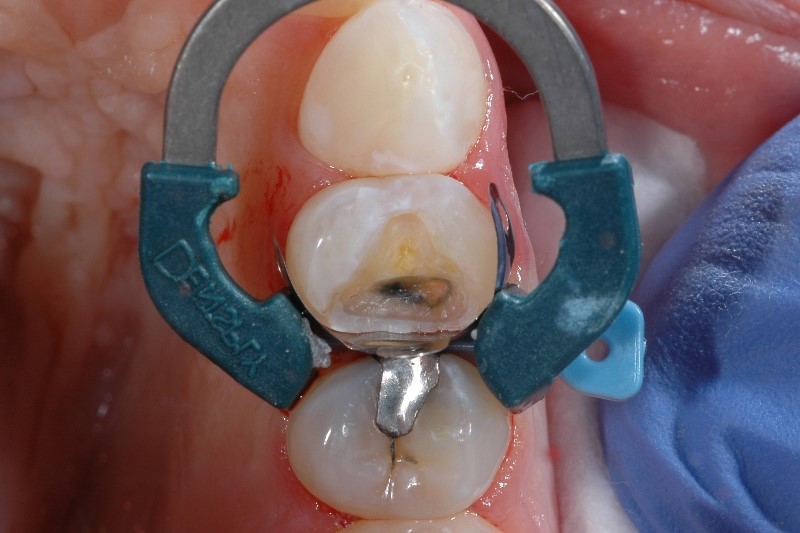

인레이는 충치를 제거하고 나서 재료로 메우는 과정입니다. 이 과정 속에서 일시적인 자극이 가해져 시린 느낌이 있을 수 있습니다. (출처: https://www.cukondental.com/)

인레이 치료는

충치 부위를 제거한 뒤

정밀하게 맞춘 보철물을 접착하는 과정입니다.

이 과정에서

충치 제거로 치아가 자극을 받았고

접착 과정 중 일시적인 민감도가 생길 수 있어요